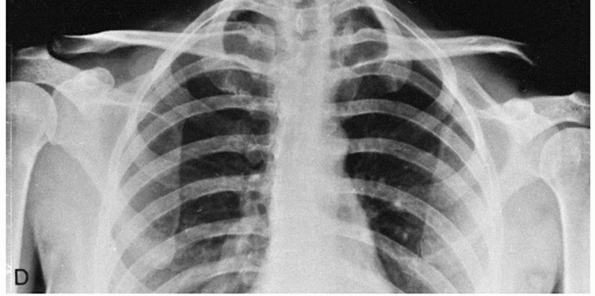

about the shoulder. Scapulothoracic dissociations are characterized by

lateral displacement of the scapula, a severe neurovascular injury, and

an injury to bone (either an AC separation, a displaced clavicle

fracture, or a sternoclavicular disruption). Scapulothoracic

dissociations are usually clinically obvious. Injuries associated with

AC separations, however, may be less obvious. The patient not only will

have pain in the shoulder but also will complain of chest pain and pain

in the periscapular and perithoracic region. Clinical examination

demonstrates the AC deformity as well as marked tenderness in the

periscapular and perithoracic region. An anteroposterior chest

radiograph demonstrates an increased distance between the medial

scapular border and the midline on the affected side compared with the

unaffected side, as well as perhaps a pleural effusion. Magnetic

resonance imaging of the thorax demonstrates increased signal in the

periscapular and perithoracic muscles in addition to a pleural effusion.